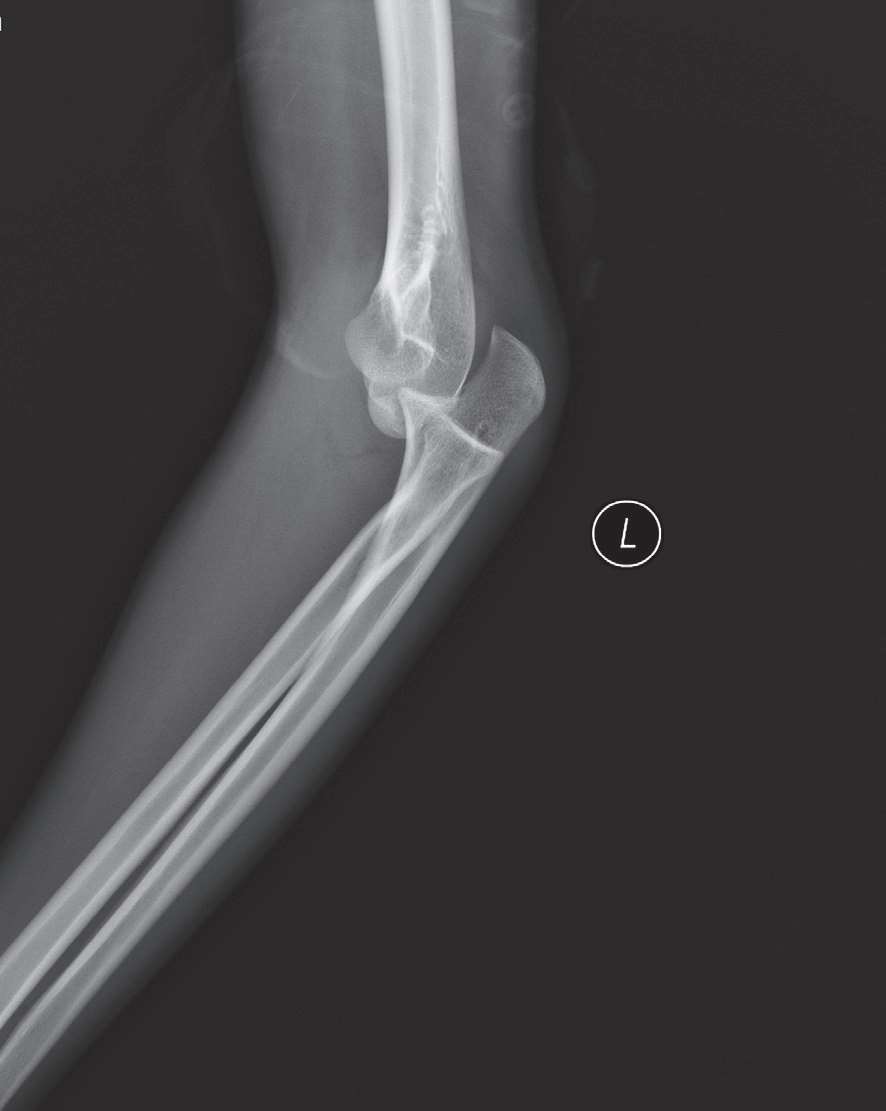

3.影像学检查(图9-1)。

图9-1 肘关节脱位X线片